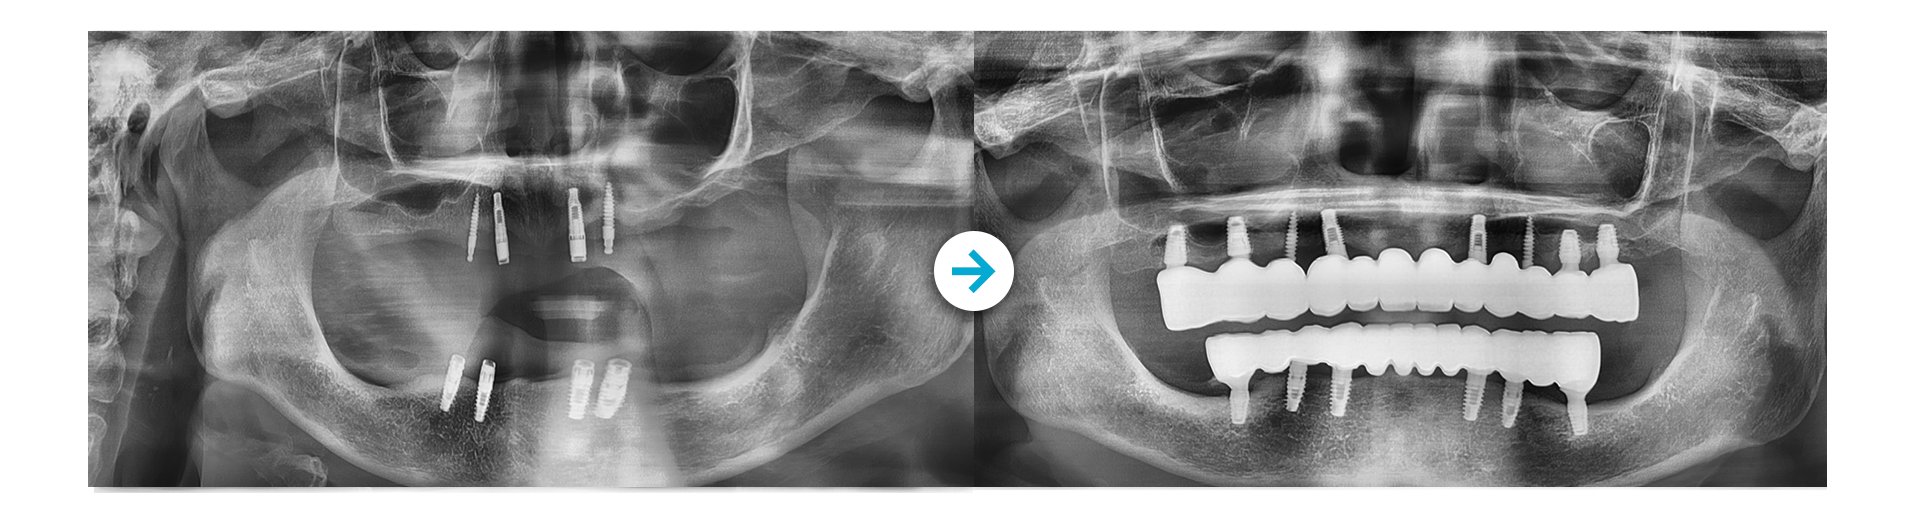

Before 사진 촬영일자: 2024.10.29 /  After 사진 촬영일자: 2025.08.15

부작용 고지: 감각이상, 신경손상, 임플란트주위염 등

* 본원에서 치료 받으신 환자분의 사례로 2차적인 가공이 없으며, 환자분의 동의를 얻어 활용함을 안내드립니다.

개인에 따라 결과차이, 부작용 등이 발생할 수 있으므로 의료진과의 상담을 통해 신중히 결정하시기 바랍니다.